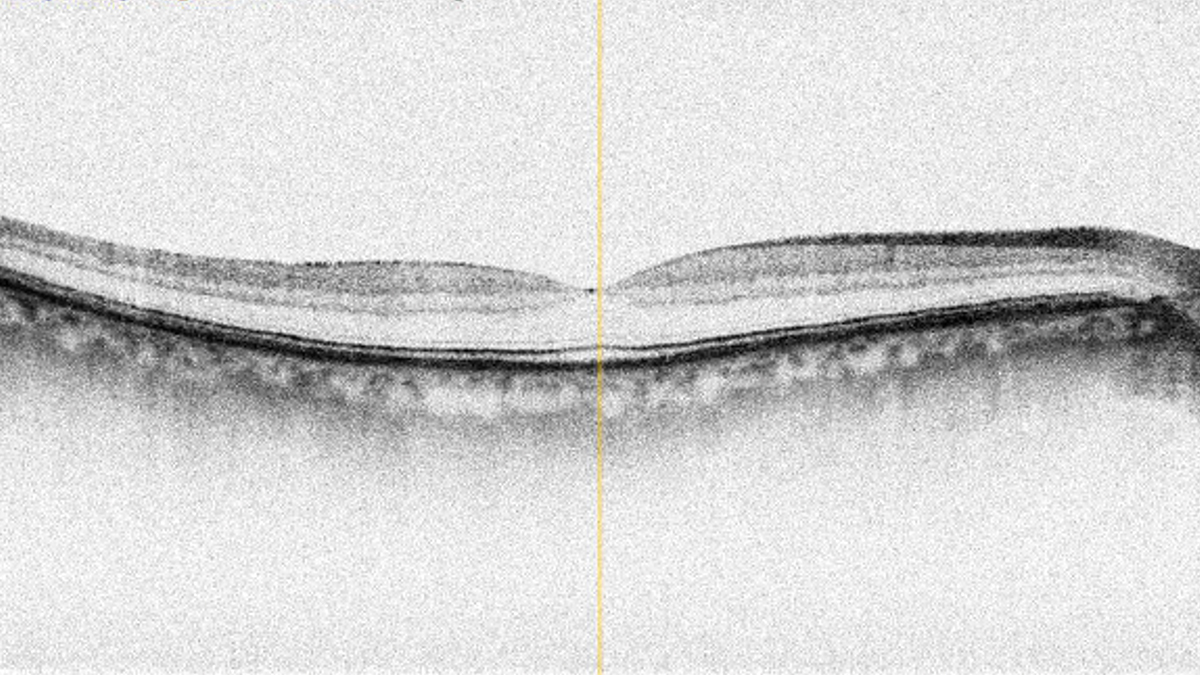

Das Coverbild der November-Ausgabe von OCL: ein OCT einer Makula